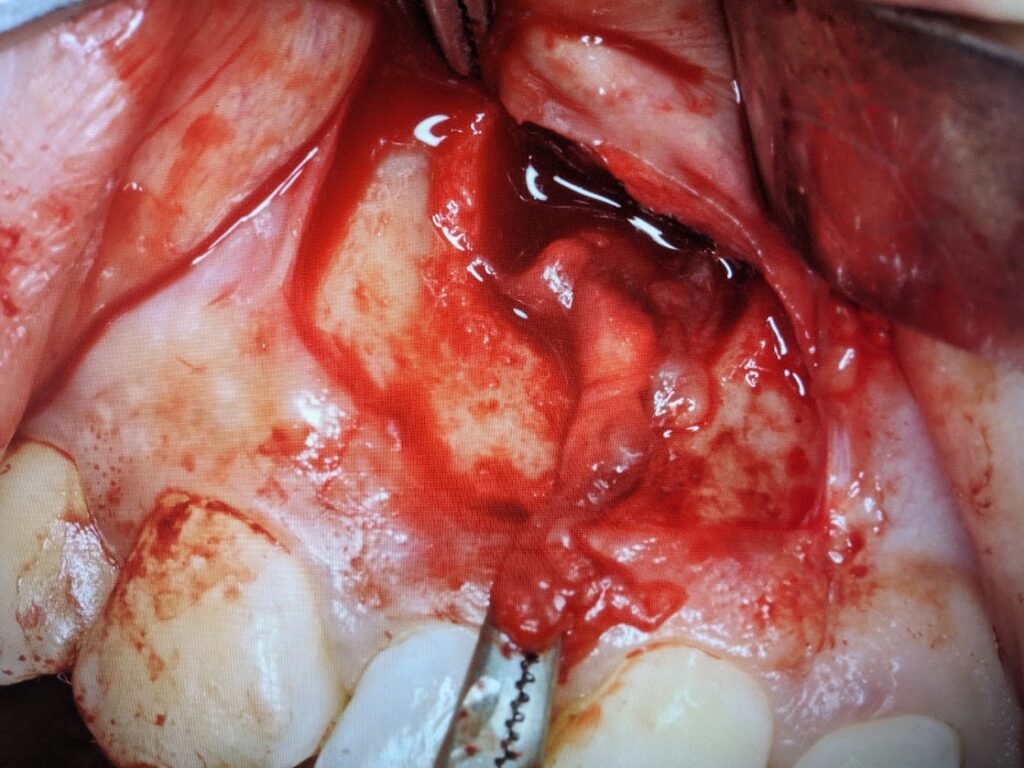

嚢胞を摘出しますと、原因である右上2の歯根が露出されます。

露出した歯根は切断し摘出します。切断面はセメントかスーパーボンドにて被覆します。(歯根端切除術)

歯根を切断しますと大きな洞穴(嚢胞腔)をみとめます。この中に残留異物がないか良く掻爬して確認します。

縫合処置を実施して手術は終了です。現在経過観察中です。